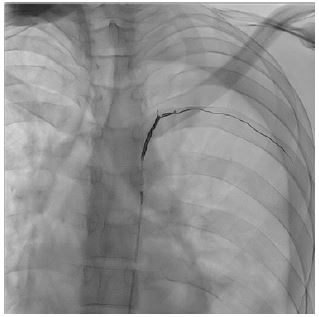

The patient underwent superselective arterial embolization of the involved intercostal artery (Figure 1). The procedure was successfully performed using microcoils (3 and 4 mm), obtaining immediate stop of bleeding (Figure 2). A left chest tube was placed and 1200 mL of blood were evacuated. The patient then underwent videothoracoscopic debridement to evacuate clots and some retained blood.

Figure 1: Angiographical embolization of intercostal pseudoaneurysm using microcoils.